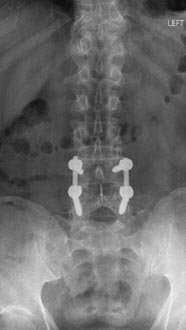

73 year old woman with osteoporosis who fell and fractured her pelvis. She was unable to walk and developed lumbopelvic dissociation (seperation of the spine from the pelvis and lower half of the body) from an unstable sacral fracture and displacement.

Lumbopelvic fixation with prophylactic cement augmentation and patient was immediately able to walk again.